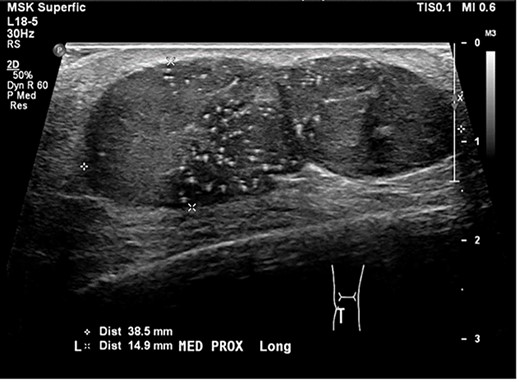

We present a case of a 35-year-old gentleman who reported a lump over his left lower leg for the last 15 years. He noticed within the last few months as it gradually increased in size with a slight discomfort, no pain or any other symptoms. He is fit and healthy apart from mild asthma which requires ventolin occasionally and he also suffers from anxiety. He has no other skin disease. Routine investigations including full blood count, urea, electrolytes and liver function tests were performed which were unremarkable. Consequently, the patient had an ultrasound which revealed bilobed solid lesion within the subcutaneous fat measuring 39x15x24 mm, suspicious for neoplasm (Fig. 1). Initially, an ultrasound-guided core biopsy was performed and it was consistent with basaloid neoplasm (Fig. 2).

an ultrasound scan shows bilobed solid lesion measuring 39x15x24 mm.